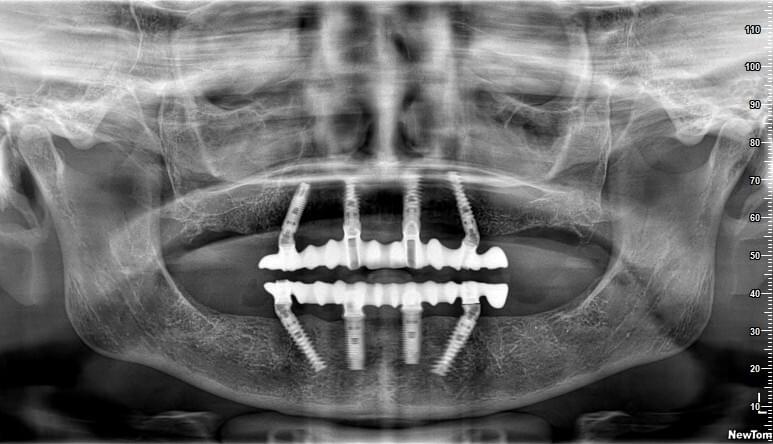

Implanturile dentare italiene sunt create pe baza rezultatelor a 10 ani de cercetări, având ca scop principal inerția ușoară și stabilitatea primară ridicată. JD Dental Care - lider mondial în domeniul implantologiei dentare ce asigură rezultate pe termen lung.

Cea mai eficientă metodă, în cazul pierderii dinților, este înlocuirea acestora cu punți sau implanturi dentare. Pentru a avea niște gingii sănătoase este recomandată inserarea implanturilor dentare peste care, în cele din urmă, se inserează coroanele dentare din Zirconiu, astfel obținând un zâmbet natural și estetic. Toată planificarea are loc cu ajutorul computerului.

Implanturi Dentare 🔥 Cazuri finisate #1